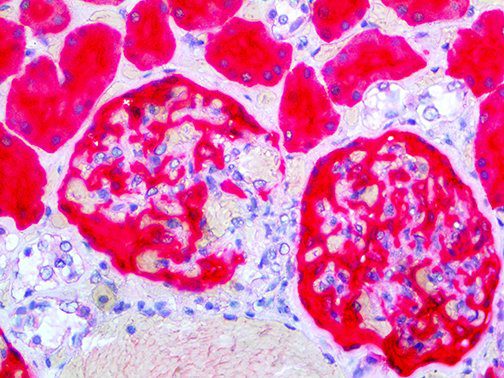

This activation induces inflammatory monocytes to highly express IL-6, starting a localized and then systemic cascade effect that results in hyperproduction of IL-6, which accelerates the inflammatory process. Because IL-6 also increases vascular permeability, excessive levels cause blood vessels to become very leaky. This, along with clotting factors released from vascular endothelial cells, stimulates the coagulation cascade, resulting in microthrombosis (tiny clots), which leads to ischemia and tissue death of the kidney, intestines, heart, liver, brain and extremities.